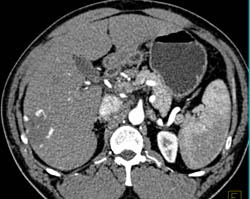

Diagnosis

Hemangioma